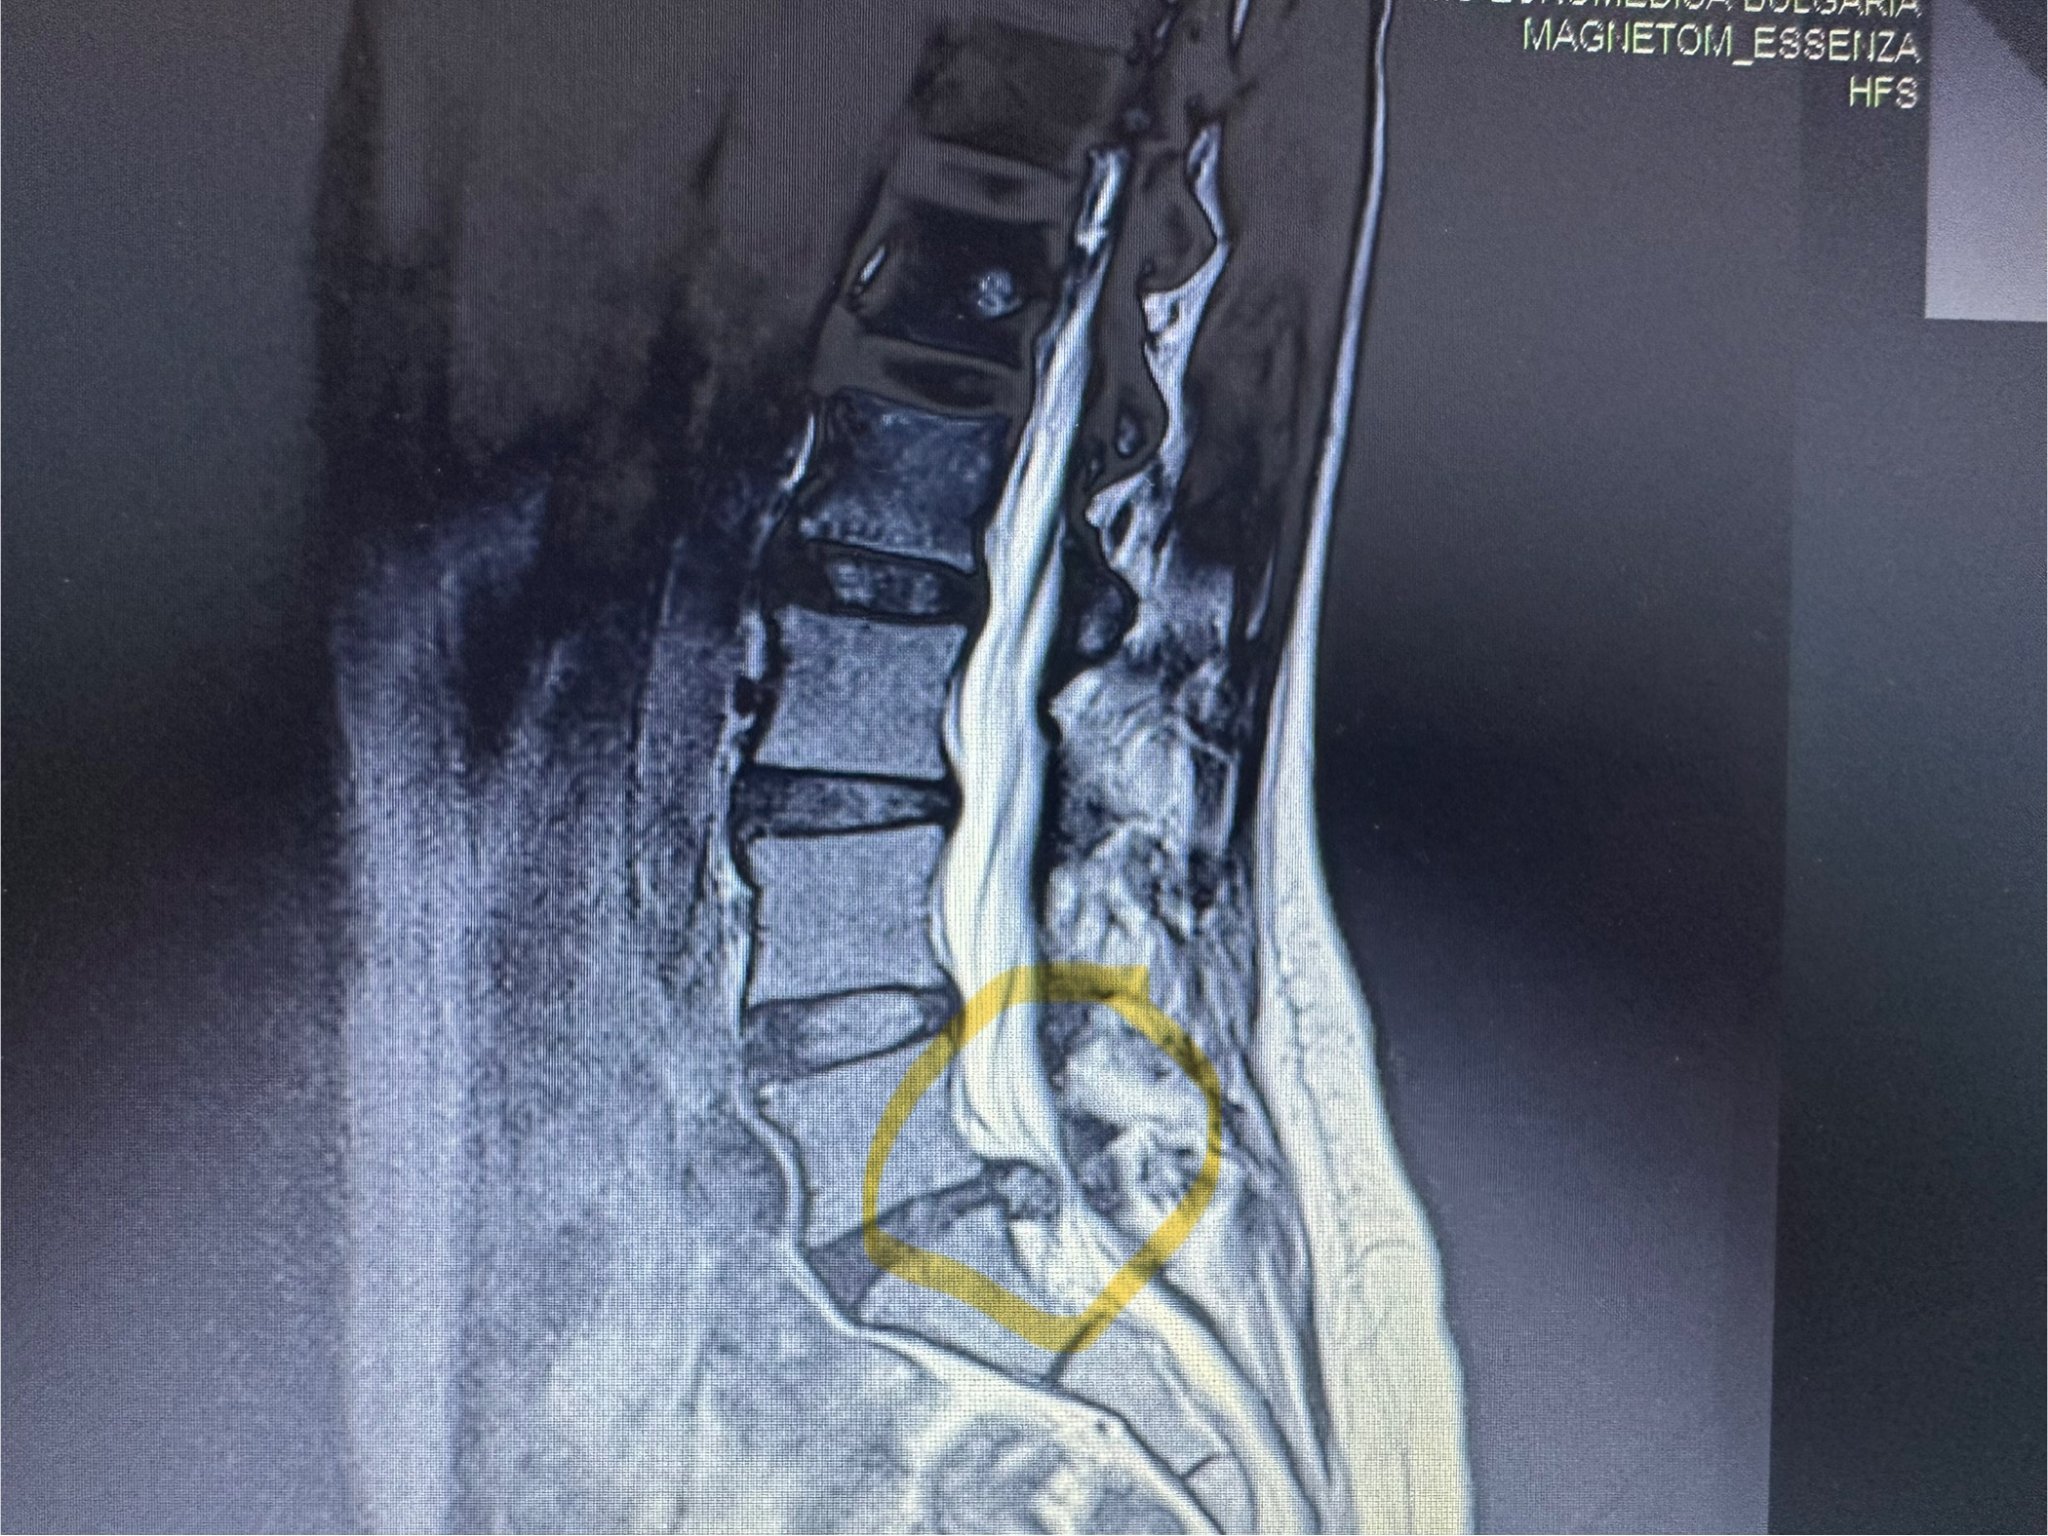

Кистите на Тарлов могат да причинят болки в кръста и краката, както и други симптоми като неврологични проблеми, инконтиненция и сексуални дисфункции. Някои лекари препоръчват наблюдение, докато други предлагат лечение като операция или медикаменти. Важно е да потърсите второ мнение и да проучите допълнителни възможности за лечение. Онлайн общностите могат да осигурят подкрепа и информация за пациенти с кисти на Тарлов.

Стана почти цяла година, откакто не съм имала ден без болка, а от вчера съм полу-инвалид. Сложиха ми мускулно Флостерон, но не бих казала, че съм много по-добре